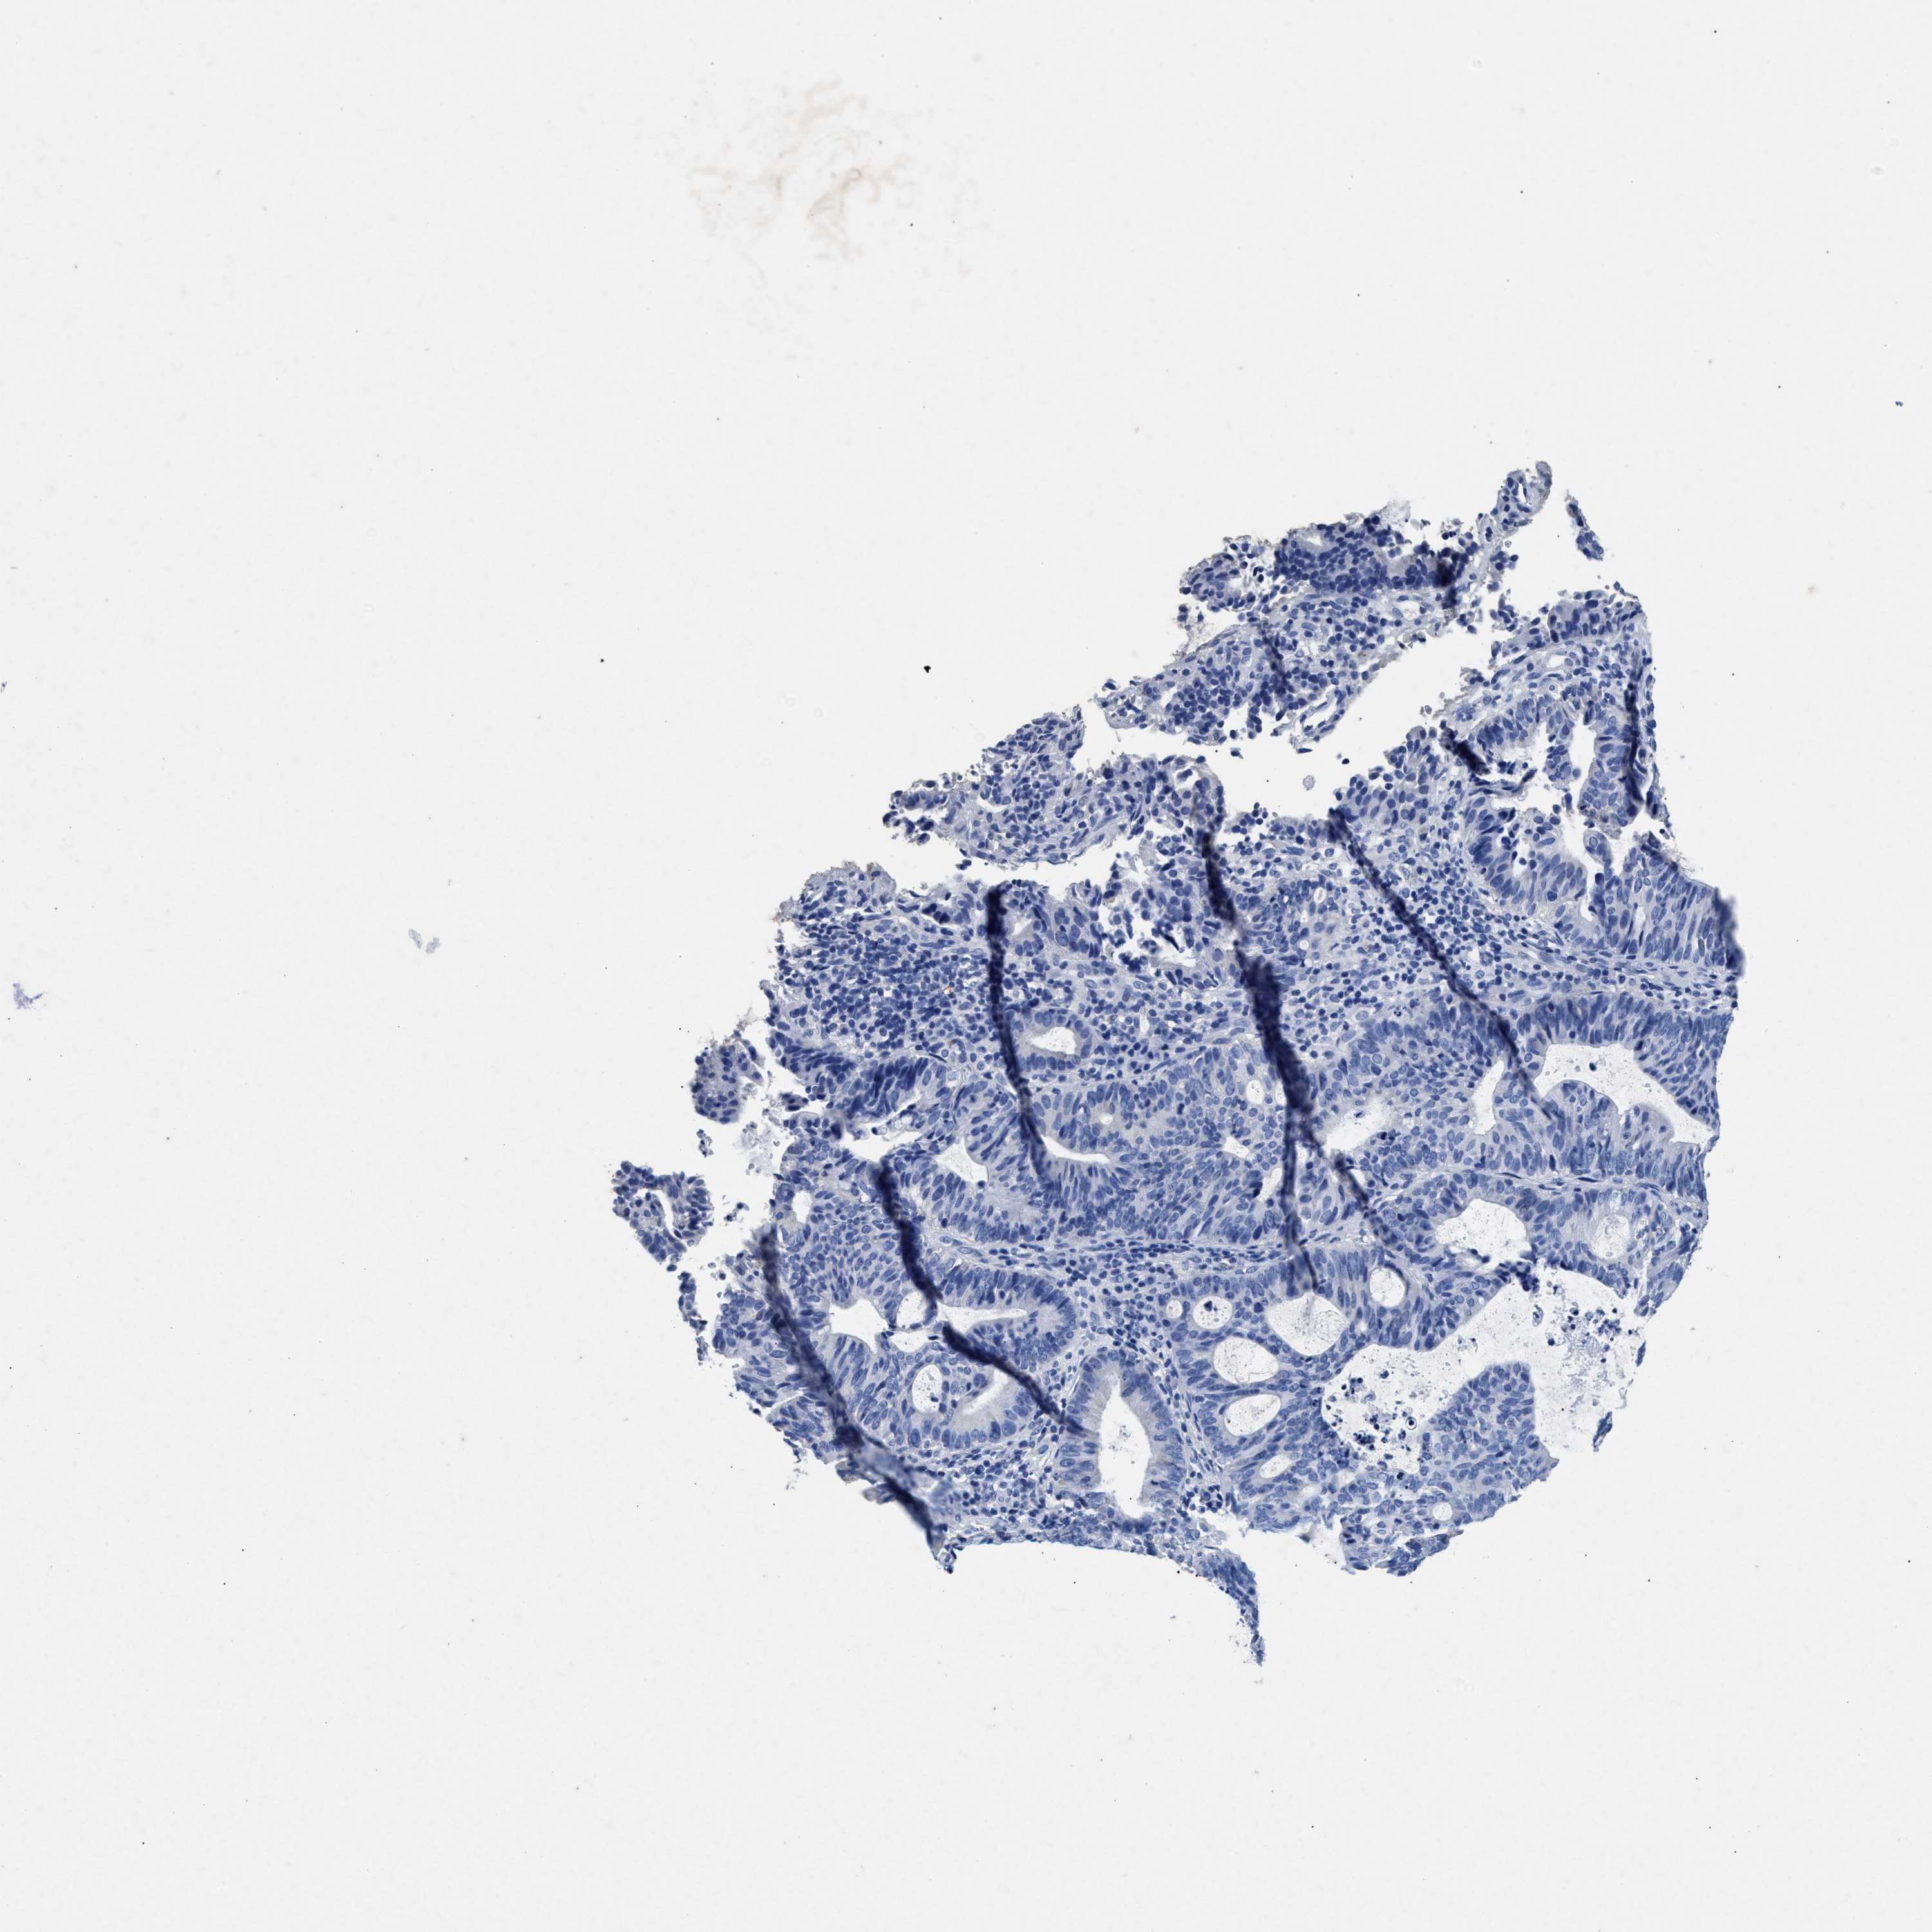

ENDOMETRIAL CANCER - Protein expressioni

A mouse-over function shows sample information and annotation data. Click on an image to view it in a full screen mode. Samples can be filtered based on level of antibody staining by selecting one or several of the following categories: high, medium, low and not detected. The assay and annotation is described here.

Note that samples used for immunohistochemistry by the Human Protein Atlas do not correspond to samples in the TCGA dataset.

Antibody stainingi

Antibody staining in the annotated cell types in the current human tissue is reported as not detected, low, medium, or high, based on conventional immunohistochemistry profiling in selected tissues. This score is based on the combination of the staining intensity and fraction of stained cells.

Each image is clickable and will lead to virtual microscopy that enables deeper exploration of all samples and also displays staining intensity scores, fraction scores and subcellular localization as well as patient and tissue information for each sample.

Antibody HPA039061

Antibody HPA039062

Antibody CAB015442

Antibody CAB022600

Staining

High

Medium

Low

Not detected

Intensity

Strong

Moderate

Weak

Negative

Quantity

>75%

75%-25%

<25%

None

Location

Nuclear

Cytoplasmic/membranous

Cytoplasmic/membranous,nuclear

Adenocarcinoma, NOS